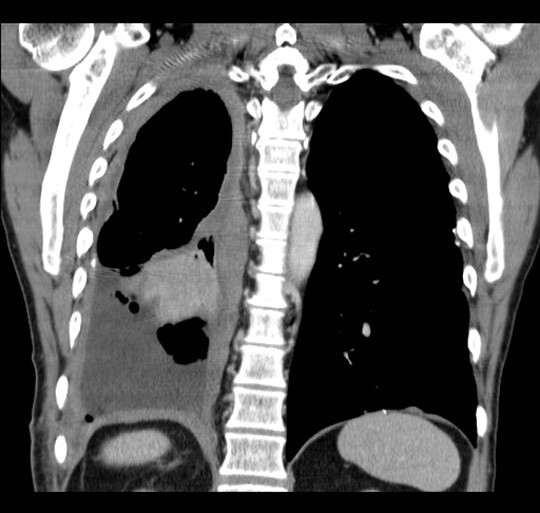

En mann i 60-årene ble utredet på bakgrunn av økende dyspné. Han hadde vært eksponert for asbest noen uker i 1970-årene, og hadde røykt fra 15 års alder. Det ble ikke funnet atypiske celler i pleuravæske. Diagnosen pleuralt mesoteliom ble fastsatt etter åpen pleurabiopsi. 18-fluorodeoksyglukose positronemisjonstomografi kombinert med computertomografi (18F-FDG PET/CT) ble rekvirert for å avklare om han kunne være kandidat for kirurgi.

18F-FDG tas opp i celler med høyt energibehov, som hjerte- og hjerneceller, betennelsesceller og maligne celler. Avbildning med PET/CT viser til venstre opptak i et malignt pleuralt mesoteliom med typisk utbredelse langs mesotelkledde hinner, her langs høyre pleura, inkludert lappespaltene. Til høyre viser CT alene de strukturelle forandringene i detalj, men skiller dårligere mellom viabelt tumorvev og benigne forandringer, som atelektase.

18F-FDG PET/CT gir mulighet for mer nøyaktig bestemmelse av sykdomsutbredelsen enn CT alene. Dette utnyttes blant annet til å selektere pasienter med begrenset sykdom for kirurgi. Ved pleurafortykkelse av ukjent årsak kan undersøkelsen være til hjelp i vurderingen av hvorvidt fortykkelsen skyldes malignitet. På grunn av lav oppløselighet har undersøkelsen imidlertid begrenset sensitivitet for små eller tynne maligne lesjoner (< 5 – 8 mm, avhengig av kamerateknologi). Tynne eller små maligne lesjoner i pleura inkludert i lappespalter kan derfor være PET-negative. Tykkere lesjoner uten opptak av 18F-FDG er mest sannsynlig benigne, selv om man må ta høyde for enkelte tumortyper som ikke tar opp stoffet.